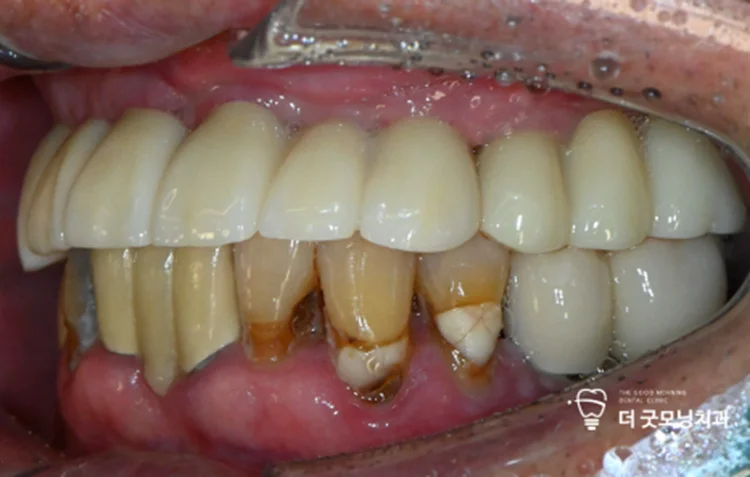

Step 7. 최종 보철 완성

임시 치아를 사용하며 약 3개월간 회복 단계를 거친 후, 충분한 고정력을 확인하고 최종 보철물을 장착하여 수면 전체 임플란트를 완성했습니다.

최종 결과 — 치료 전후 비교